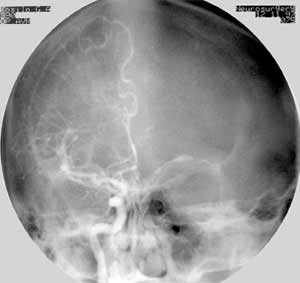

Дигитальная субтракционная ангиография.

Рис. 1 и 2. Артерио-венозная мальформация в правой теменной области, заполняющаяся из передней и средней мозговых артерий. Артериальная фаза. Фронтальная проекция.

(Слева) Классическая ангиограмма. (Справа) Дигитальная субтракционная ангиограмма того же пациента. Изображение костей черепа "стерто". При меньшем расходе контрастного вещества сосудистая сеть видна гораздо лучше.